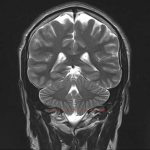

- КТ и МРТ помогают послойно оценить состояние головного мозга. Это позволяет обнаружить заболевания, которые могли бы стать причиной инсомнии.